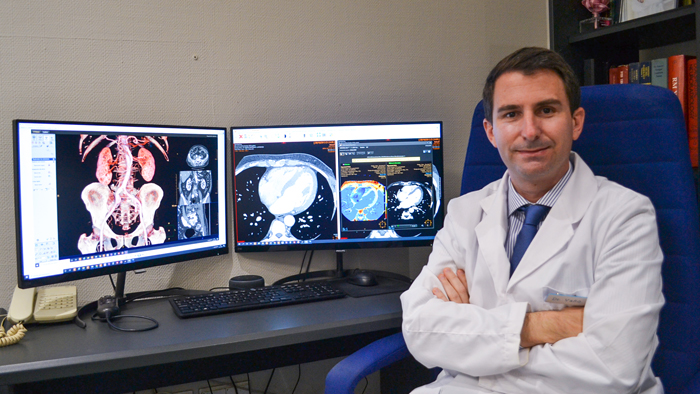

Campus Bio-Medico University Hospital increased reading productivity by 50% with the allocation of the right exam to the right professional.4

Hospital Nuestra Señora del Rosario saved 1-2 minutes per patient through integrated workflow within a single workspace for radiologists.5